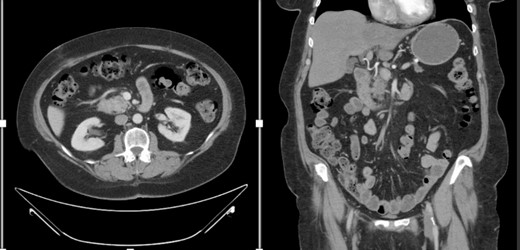

A female in her 60s presented with a 6-month history of progressive abdominal cramping, acholic stools, early satiety, post-prandial loose stools and flatulence. She reported a history of newly diagnosed diabetes mellitus with progressively difficult-to-control hyperglycemia requiring initiation of GLP-1 agonist therapy within the preceding year. She was a former cigarette smoker with 15 pack years’ history and no reported other substance use history. Basic hematological test was normal. Colonoscopy done showed no significant findings. A CT abdomen and pelvis with contrast identified a hypodense 1.5-cm solid mass in the pancreatic head with abutment of the superior mesenteric vein without arterial abutment or regional lymphadenopathy (Fig. 1); proximal main pancreatic duct dilatation and pancreatic parenchymal atrophy in the neck, body and tail. An endoscopic ultrasound identified a 2.8-cm hypoechoic partially circumscribed 1.5-cm mass in the pancreatic head. Core biopsy demonstrated poorly differentiated adenocarcinoma (PanKeratin, S100p, DOG-1, CK-7 positive; Ki67 20–30%). A staging CT chest and pancreatic protocol demonstrated an interval increase of the solid pancreatic head mass to 2.5 cm without other abnormalities (Fig. 1). Baseline serum Cancer Antigen 19-9 was non-elevated (3.02 U/mL). She was staged as a cT2N0M0 (Stage IB) pancreatic adenocarcinoma prior to therapy. Germline genetic testing demonstrated variants in KRAS, CDKN2A and TP53 with variant allele fraction of 25, 24.85 and 20.3%, respectively. Microsatellite instability was stable with a tumor mutation burden of 3.2 m/MB. She was initiated on pancreatic enzyme replacement therapy with resolution of her presenting symptoms and glycemic control was achieved with GLP-1 agonist therapy. The patient was referred for Genetic counselling.

CT abdomen and pelvis with IV contrast with axial and coronal views demonstrating the Pancreatic mass.

She completed nine cycles of mFOLFIRINOX systemic therapy, requiring a 50% irinotecan dose reduction at cycle 3 and a 75% reduction at cycle 4 due to neurocognitive side-effects. She discontinued systemic therapy after cycle 9 due to progressive chemotherapy-associated steatohepatitis and fatigue. Repeat staging imaging demonstrated a RECIST 1.1 radiographically stable disease (12% reduction in the primary tumor diameter).